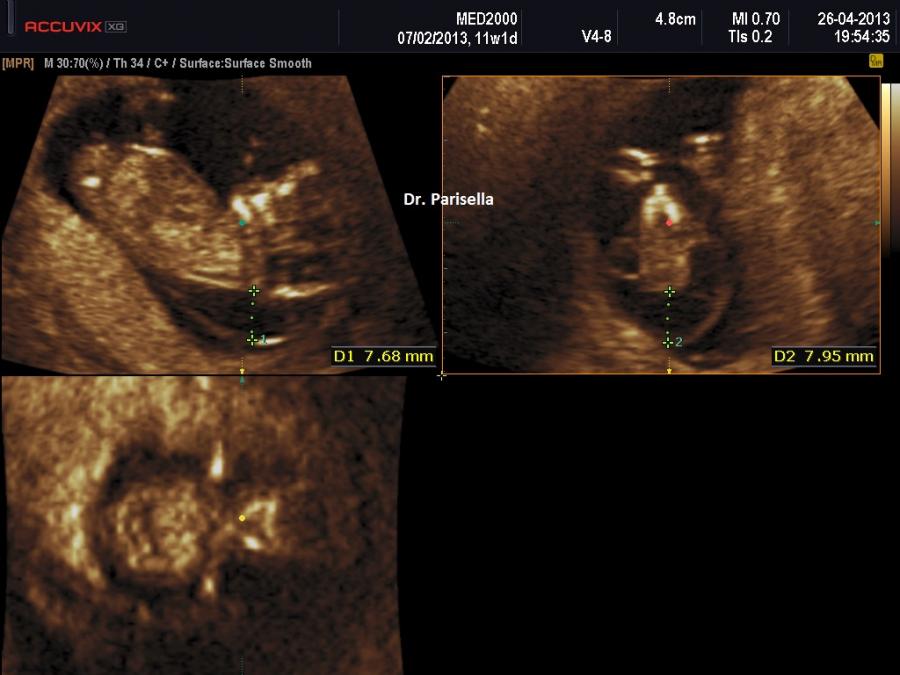

L'igroma cistico in genere viene diagnosticato intorno alla 12a-14a settimana di epoca gestazionale per la presenza di una formazione cistica localizzata nella regione postero-laterale del collo fetale. Può essere settato o non settato. L'evoluzione è varia: può progredire verso l'idrope fetale generalizzata, può persistere come edema nucale, può regredire completamente; i casi che vanno incontro a regressione sono interpretabili come conseguenza di una ostruzione transitoria o come un ritardo nello sviluppo della comunicazione tra sacco linfatico laterocervicale e vena giugulare.